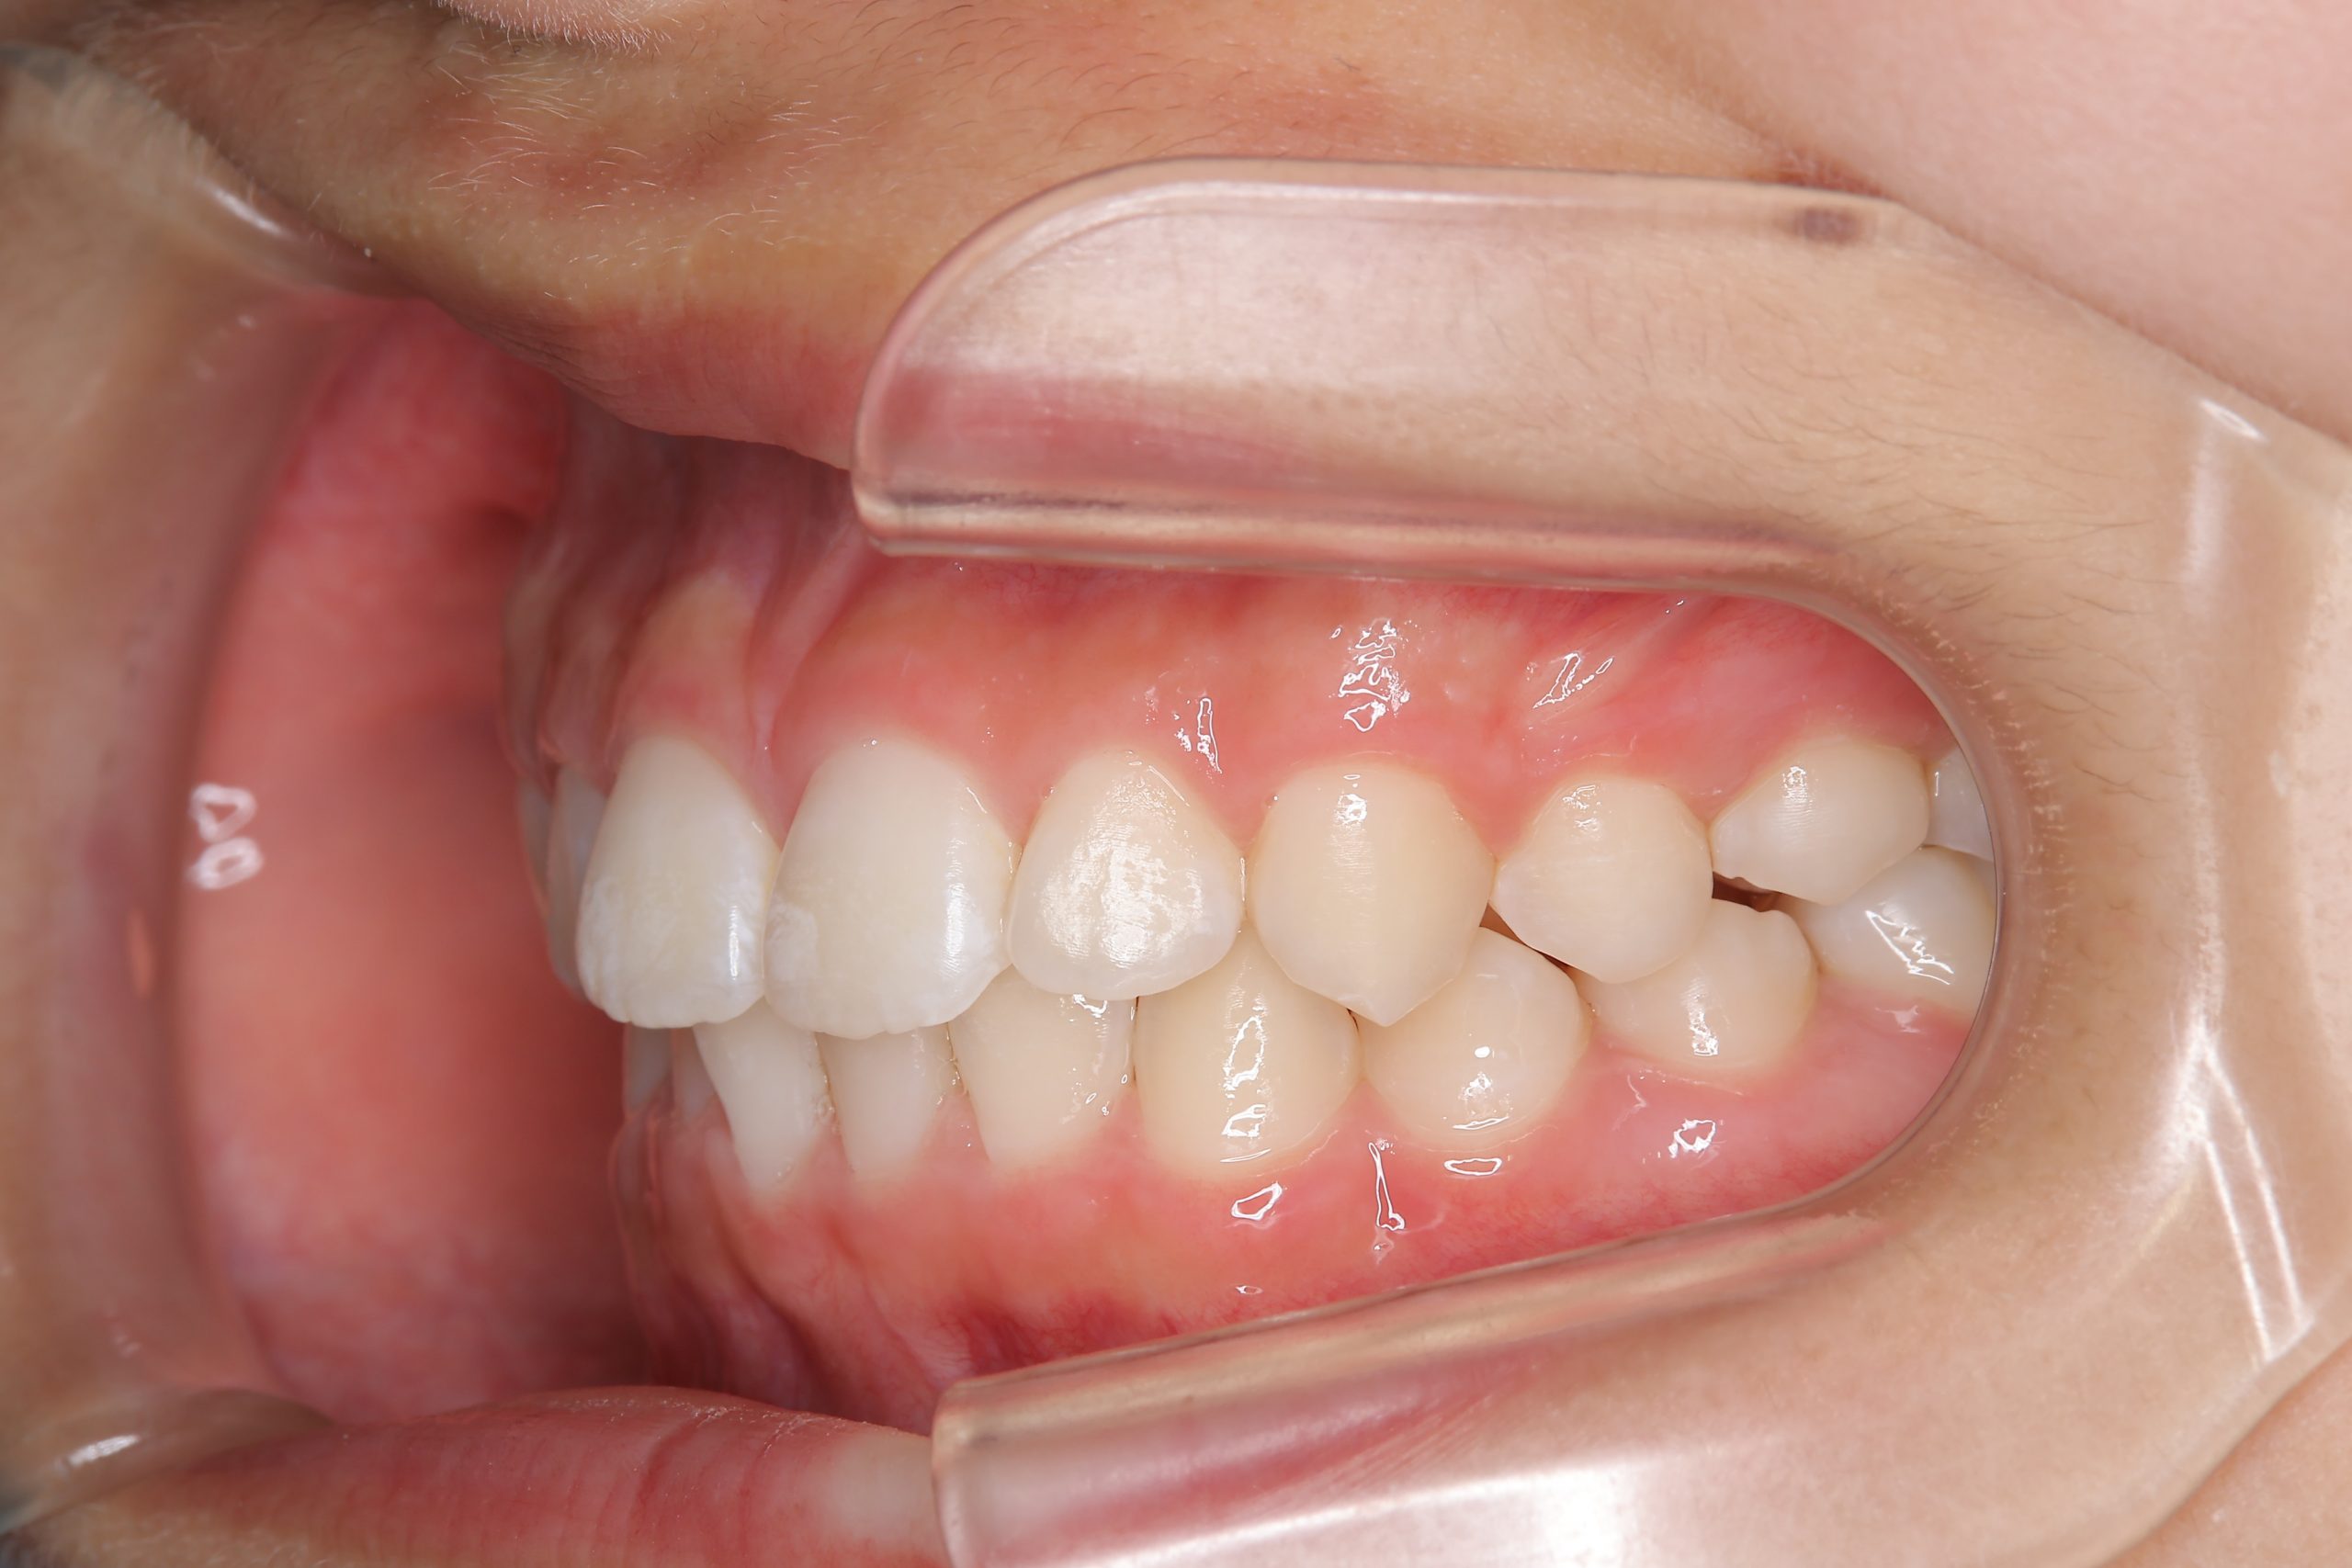

全顎ワイヤー矯正 症例_610 Case

ビフォー

| 主訴 | 前歯の歯並び|歯ぎしり |

| 施術内容 | 小児矯正1期治療 |

| 治癒期間 | 2年4か月間 |

| 費用 | 711,700円(税込) |

| リスク・副作用 | 違和感、不快感、痛み |